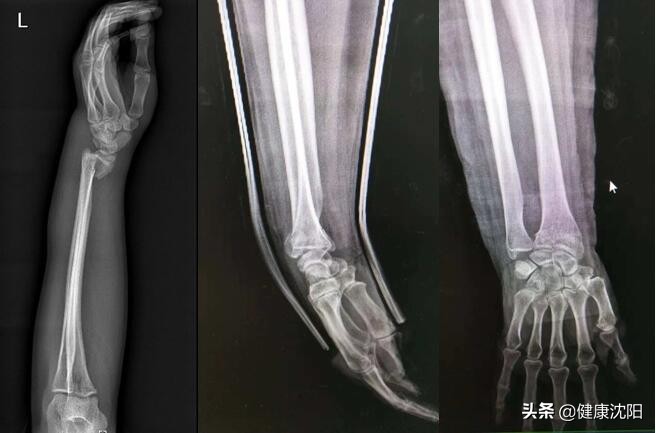

为了确诊,医生将会建议患者拍腕关节X片。X片是最常见的、应用十分广泛的影像诊断技术,它可以显示骨头是否骨折以及是否移位(骨折端的间隙),同时可以显示里面

有多少骨折块。